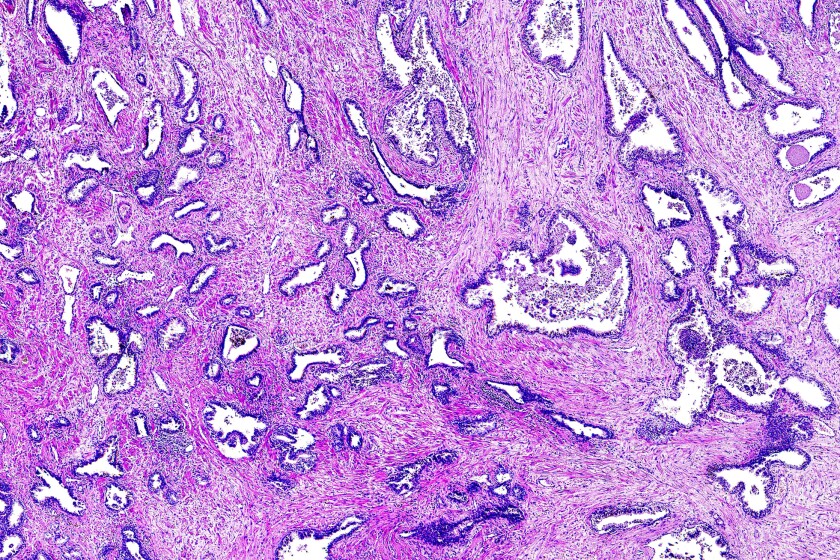

| Các nhà nghiên cứu đã tìm thấy ba dấu ấn sinh học ung thư tuyến tiền liệt mới sẽ hỗ trợ các nhà nghiên cứu bệnh học đánh giá chính xác mức độ nghiêm trọng của bệnh |

Điểm Gleason là điểm chính trong việc xác định mức độ ung

thư tuyến tiền liệt. Một nhà nghiên cứu bệnh học quan sát các tế bào ung

thư nhuộm màu dưới kính hiển vi để xem chúng trông giống tế bào khỏe mạnh như

thế nào (chúng được điểm thấp) hay tế bào bất thường và xâm lấn (điểm

cao). Điều này cho thấy khả năng ung thư sẽ tiến triển và lan rộng như thế

nào. Ung thư có điểm thấp phát triển chậm hơn và ít có khả năng lây lan

hơn ung thư có điểm cao.